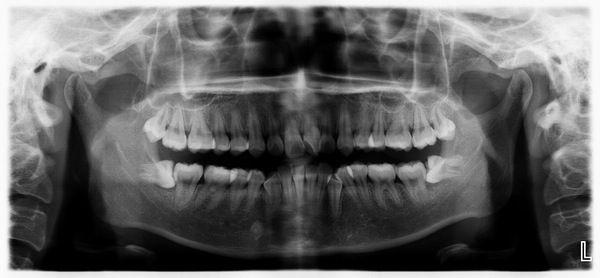

人一生有两套牙齿,乳牙和恒牙。 恒牙全部出齐共有32枚,排列在最后面的那个牙(上、下、左、右共4枚)因为生出来的时间最晚,一般都是到了成年期才长出来,所以被称为“智齿”。 智齿每个人都有,区别在于,有的人的智齿长得露出来了,有的人的智齿虽然长了,但没头来。 但现代人类的颌骨由于食物的越来越精细而发育偏小,所以最后面的那个牙的生长空间不足,在萌出时由于挤压周围结构会产生疼痛。必要时不得不将其拔除。

首先说一下,智齿每个人都会长的。 医学常识说智齿就是人成年后开始长出的牙齿,一般人在幼年期间乳牙脱落之后长出的牙齿有28个,成人还会长4颗,就成了32颗,那就说明你长大成人啦! 在医学上,智齿又叫第三磨牙,从前往后数的第八颗牙,智齿是人类三十二颗恒牙当中,最后长出的恒牙,位于上下左右牙弓的最后方。因为在智齿长出时大多会在十六到二十四岁左右,在人的智慧成长后,所以又有智慧齿之称, 简称智齿。 人类在进化过程中由于食物越来越精细,颌骨承受的负担相应减少,导致颌骨骨量不断减少,但牙齿的体积并不随之减小,最终使牙齿萌出的位置不足,最后萌出的第三磨牙最易形成智齿冠周炎,这是智齿萌出位置异常最主要的原因。 智齿的由来智齿是指人类口腔内,牙槽骨上最里面的上下左右各一的4颗第三磨牙。因为这4颗第三磨牙正好在20岁左右时开始萌出,此时人的生理、心理发育接近成熟,于是被看做是"智慧到来"的象征,故称它为"智齿"---智慧之齿。 其实,从现代医学的观点看,智齿是人类进化的必然。众所周知,"用进废退"是生物进化论中的一个普遍规律。智齿就是极好的例证。

有没有长智齿,回家拿起镜子,大张嘴,从门牙(切牙)开始数,第八颗是智齿。 由于古猿和古人类的食物质地都很坚硬粗糙,比如树枝、植物块茎、动物的肌肉、筋腱等,在咀嚼的时候要求要有较大的力量和更大的碾磨面积,所以古猿和古人类的颌骨较大以承受咀嚼食物时候的咬合力量,智齿的存在并且正常行使功能,对于增加咀嚼效率非常重要。 在人类的进化过程中,由于食物不断的精细化,咀嚼食物时的咬合力也随之不断减小,使得颌骨没有得到足够的刺激,所以颌骨发育的也越来越小。正由于颌骨的变化,现代人的颌骨提供的可以供牙齿萌出的空间已经大大缩小,这样智齿在萌出时往往会因为空间不足而导致异位萌出、阻生。萌出的困难常常导致难以忍受的疼痛,或者导致智齿冠周炎,以至于很多人谈起长智齿的过程,往往“说多了都是眼泪”。即使有的好不容易萌出了,但因为位置偏差,也不能与对(牙合)的牙齿形成稳定有效的咬合关系,所以不能进行咀嚼。 所以智齿实际上是人类演化过程中被放弃的生物学性状,由于个体遗传基因的不同,在这个性状的表达上是有差异的。目前这个进化过程还未结束,虽然有一部分人智齿的牙胚消失了,但大部分人出生时都有智齿的牙胚,但是萌出时会有不同